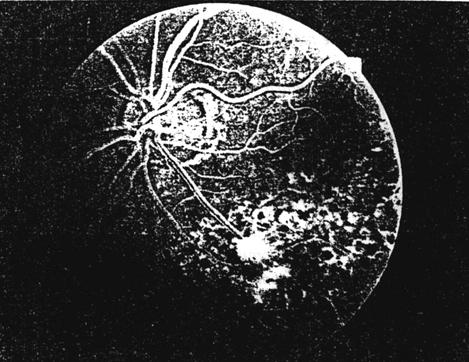

fig. 8

FAG - OVCR forma nonischemica